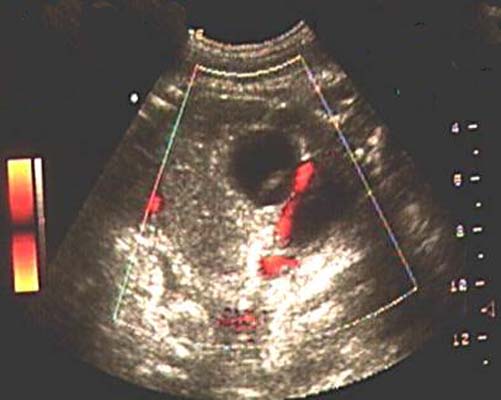

Artère ombilicale unique